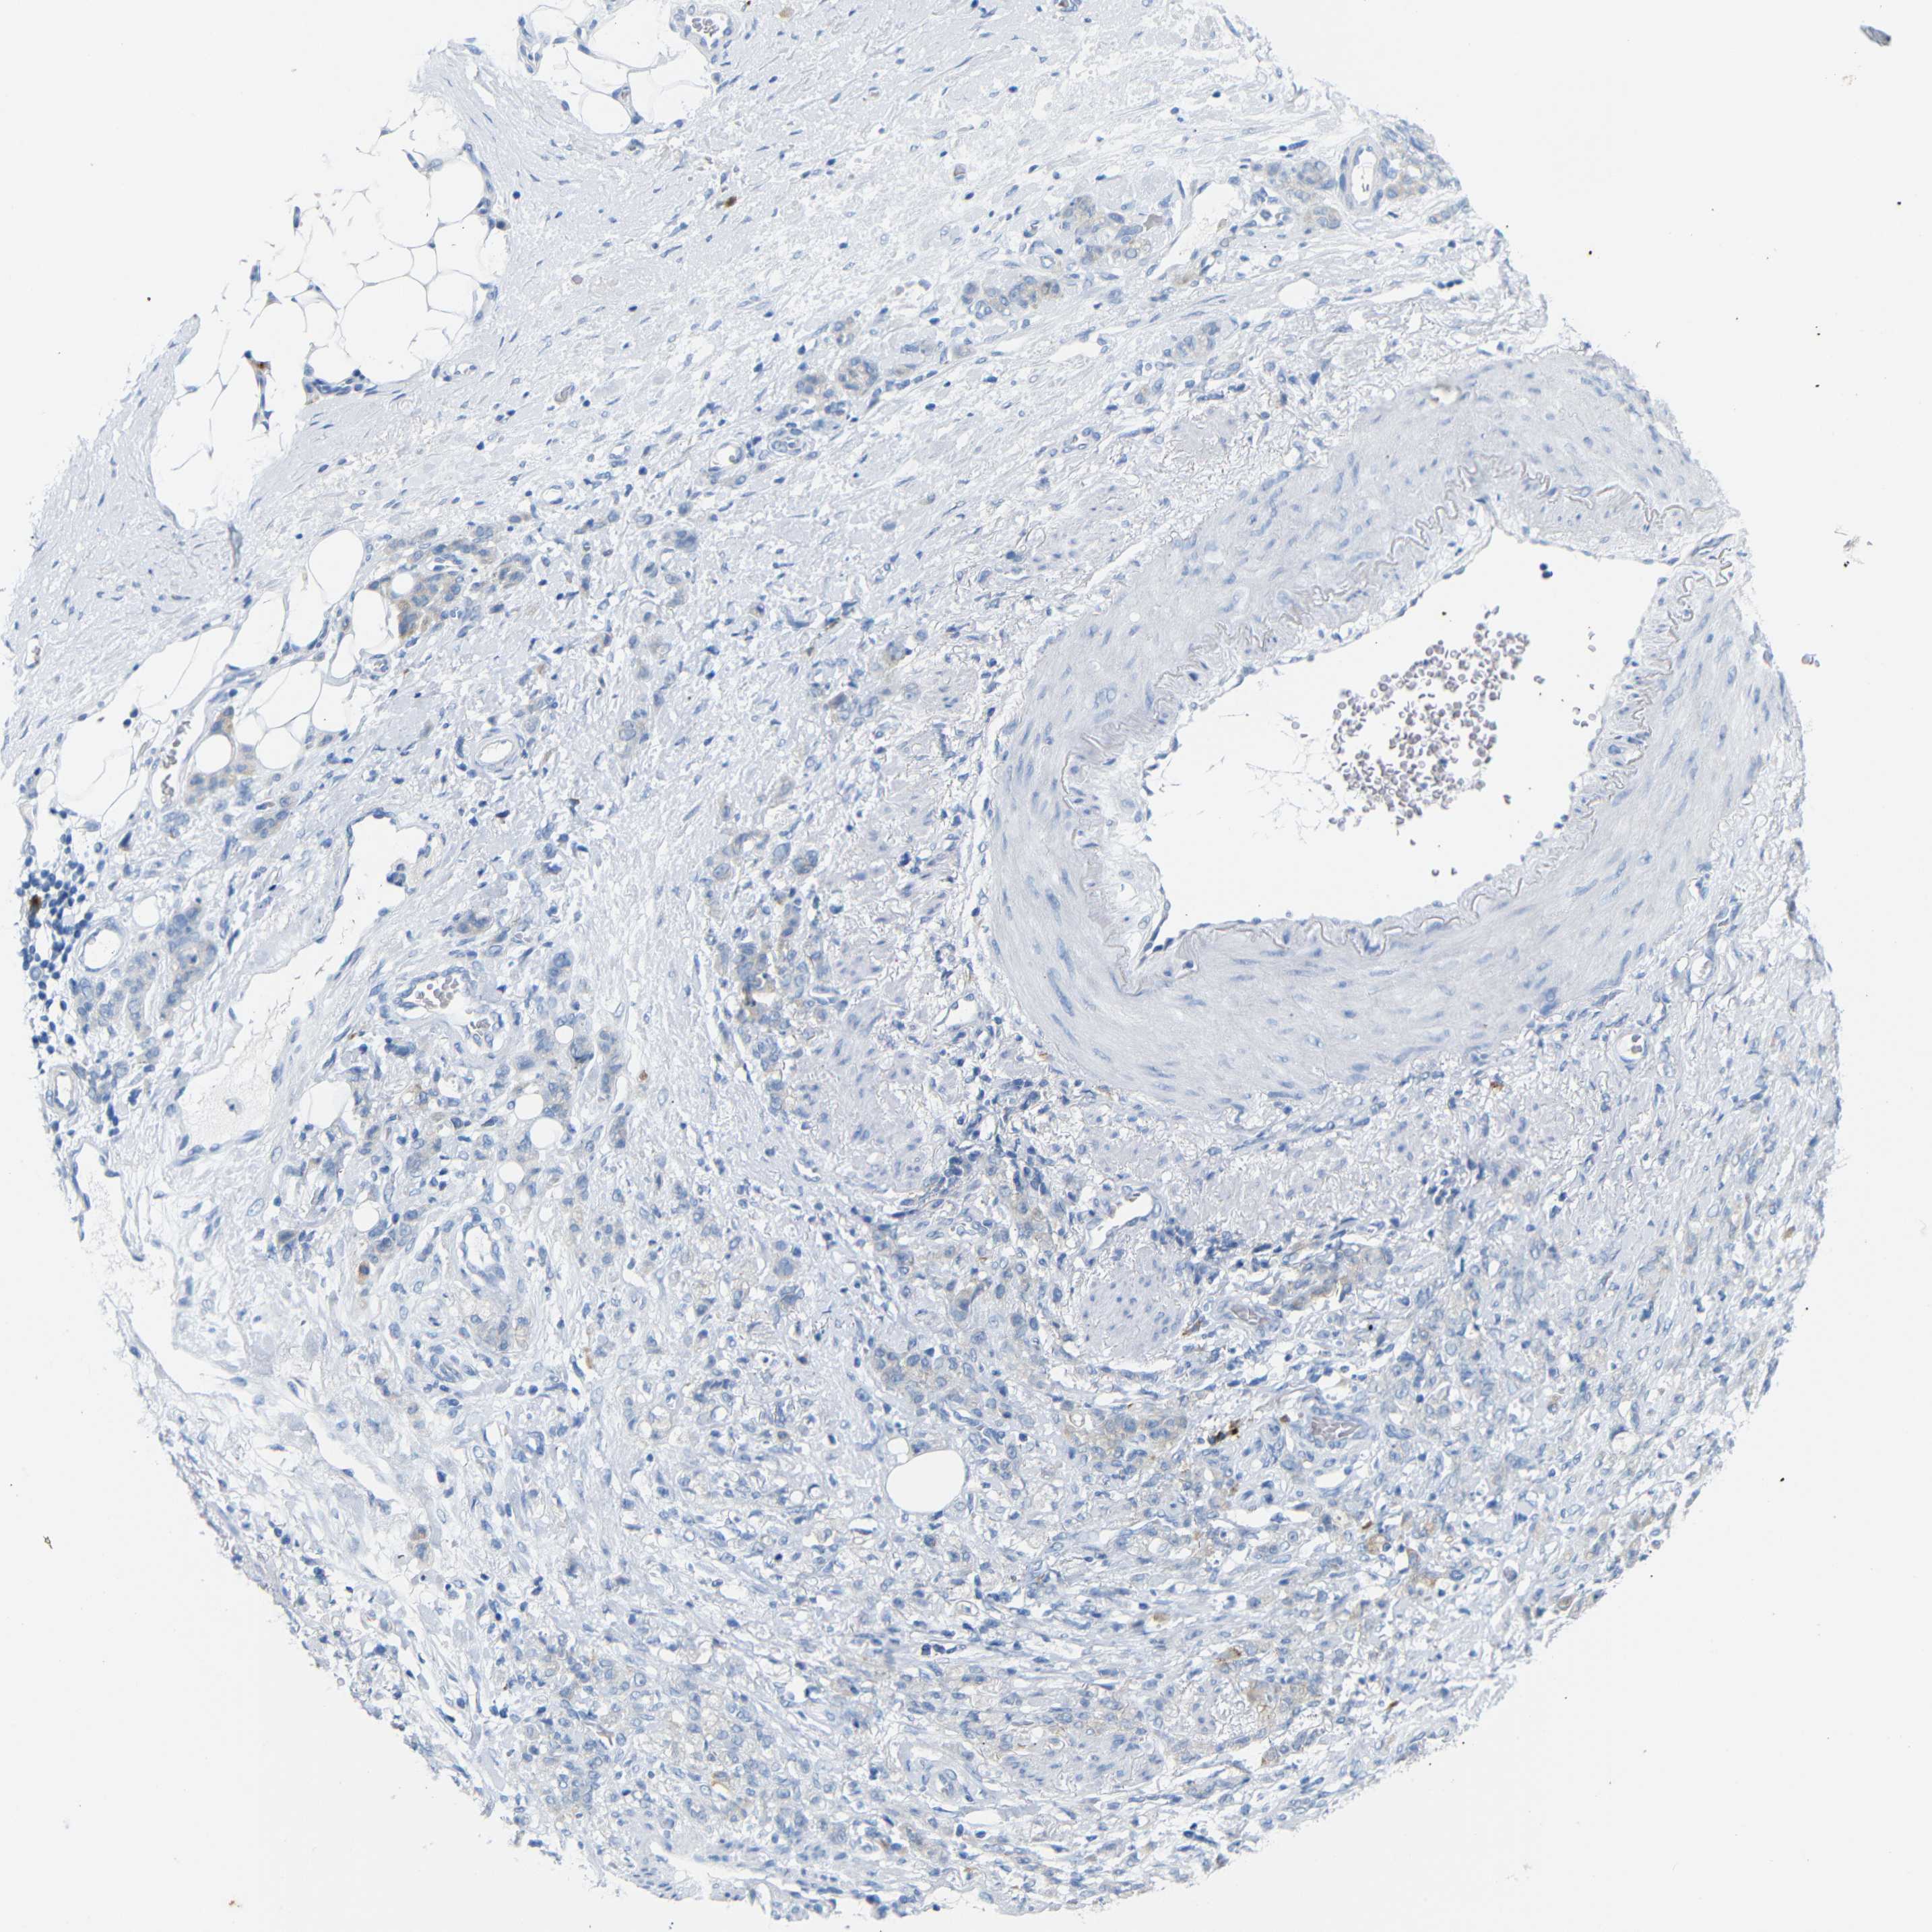

STOMACH CANCER - Protein expressioni

A mouse-over function shows sample information and annotation data. Click on an image to view it in a full screen mode. Samples can be filtered based on level of antibody staining by selecting one or several of the following categories: high, medium, low and not detected. The assay and annotation is described here.

Note that samples used for immunohistochemistry by the Human Protein Atlas do not correspond to samples in the TCGA dataset.

Antibody stainingi

Antibody staining in the annotated cell types in the current human tissue is reported as not detected, low, medium, or high, based on conventional immunohistochemistry profiling in selected tissues. This score is based on the combination of the staining intensity and fraction of stained cells.

Each image is clickable and will lead to virtual microscopy that enables deeper exploration of all samples and also displays staining intensity scores, fraction scores and subcellular localization as well as patient and tissue information for each sample.

Antibody HPA013323

Staining

High

Medium

Low

Not detected

Intensity

Strong

Moderate

Weak

Negative

Quantity

>75%

75%-25%

<25%

None

Location

Nuclear

Cytoplasmic/membranous

Cytoplasmic/membranous,nuclear

Adenocarcinoma, NOS

Adenocarcinoma, High grade